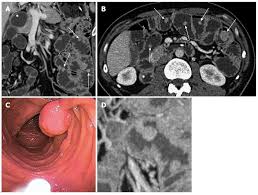

A And B Peutz Jeghers Syndrome In 22 Year Old Woman Contrast Study Download Scientific Diagram

Surveillance Of Polyps In A 27 Year Old Man With Peutz Jeghers Download Scientific Diagram